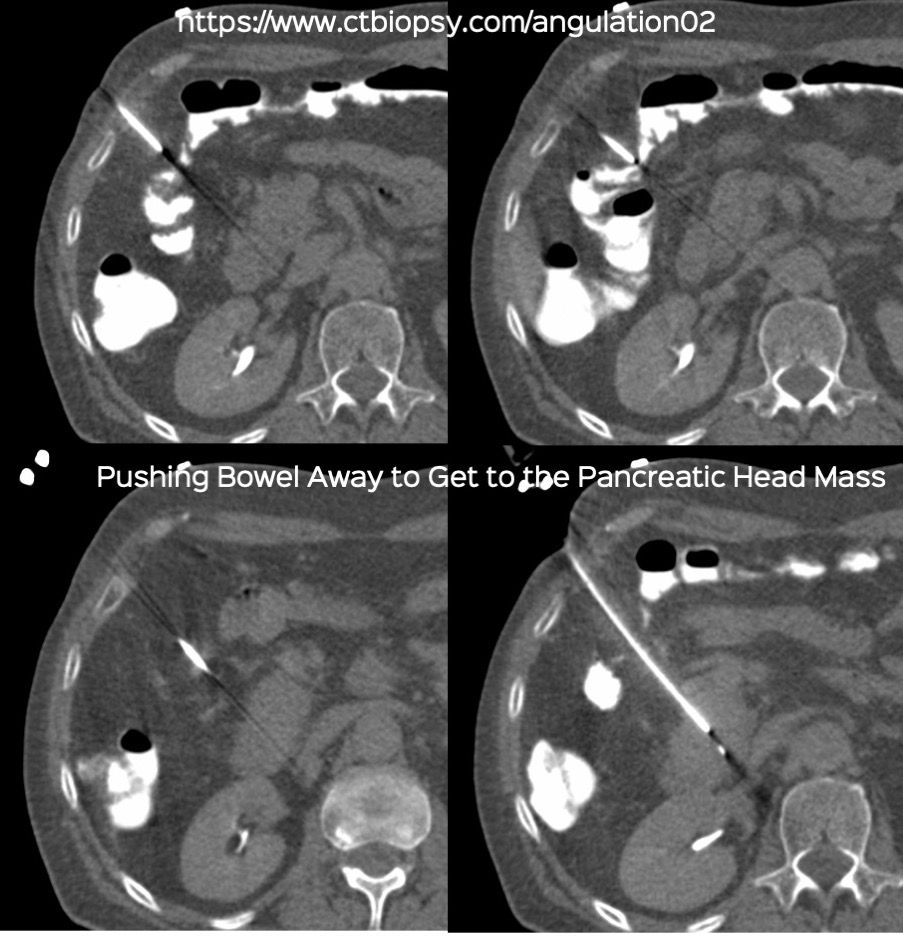

Case 82: Displacing Bowel